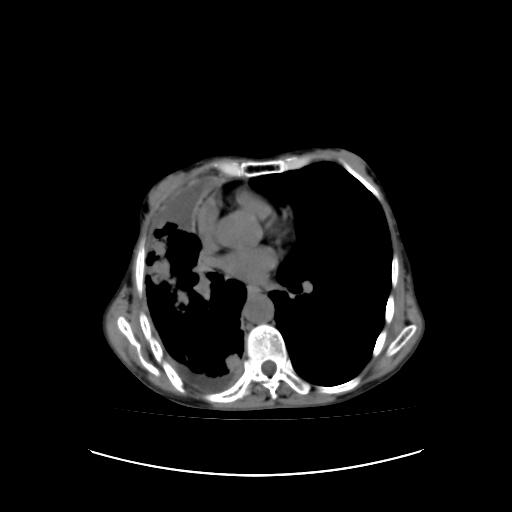

标题: CT16930:女 59 胸痛6个月 胸水脱落细胞学见瘤细胞 [打印本页]

标题: CT16930:女 59 胸痛6个月 胸水脱落细胞学见瘤细胞

可见多发肺内病灶,且胸膜病灶较多有圆球状而非丘状,多考虑胸膜转移瘤伴胸腔积液,右侧胸廓缩小固定,且部分病灶呈丘状,尚不除外恶性胸膜间皮瘤伴肺内转移

右侧胸廓塌陷,右侧胸膜广泛增厚并见多发胸膜结节,右侧少量胸腔积液并包裹。

胸膜转移瘤  包裹性胸腔积液  肺内转移

右胸腔结节均考虑来自胸膜(部分来源于叶裂),考虑胸膜间皮瘤或转移瘤.